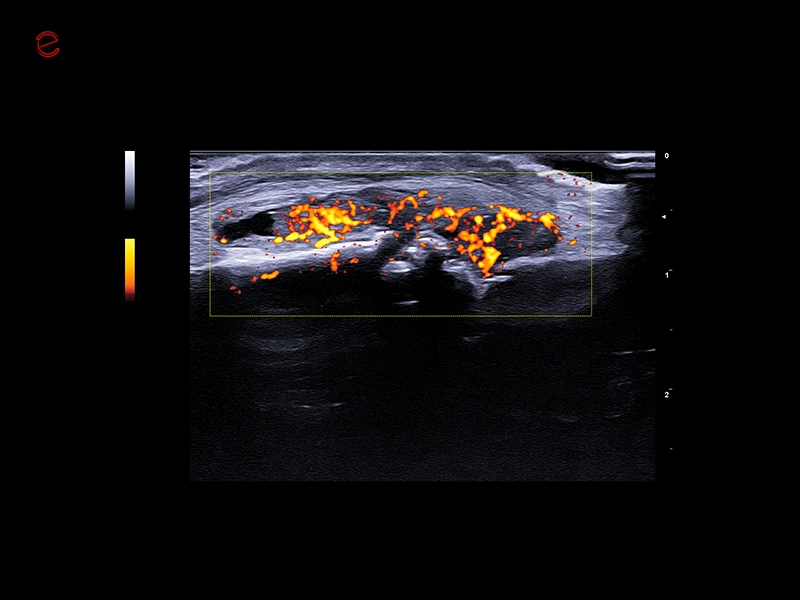

IDEAL FOR A VARIETY OF CLINICAL APPLICATIONS

High-quality imaging on-the-go

A compact and dependable partner, the MyLab™C25 is designed to support your daily practice with ease, providing high-quality imaging for confident diagnostics every time. With MyLab™C25 and its wide range of probes, we provide you with the ability to perform examinations in a broad variety of clinical applications such as general imaging, superficial scanning, cardiology, vascular, gynecology and obstetrics